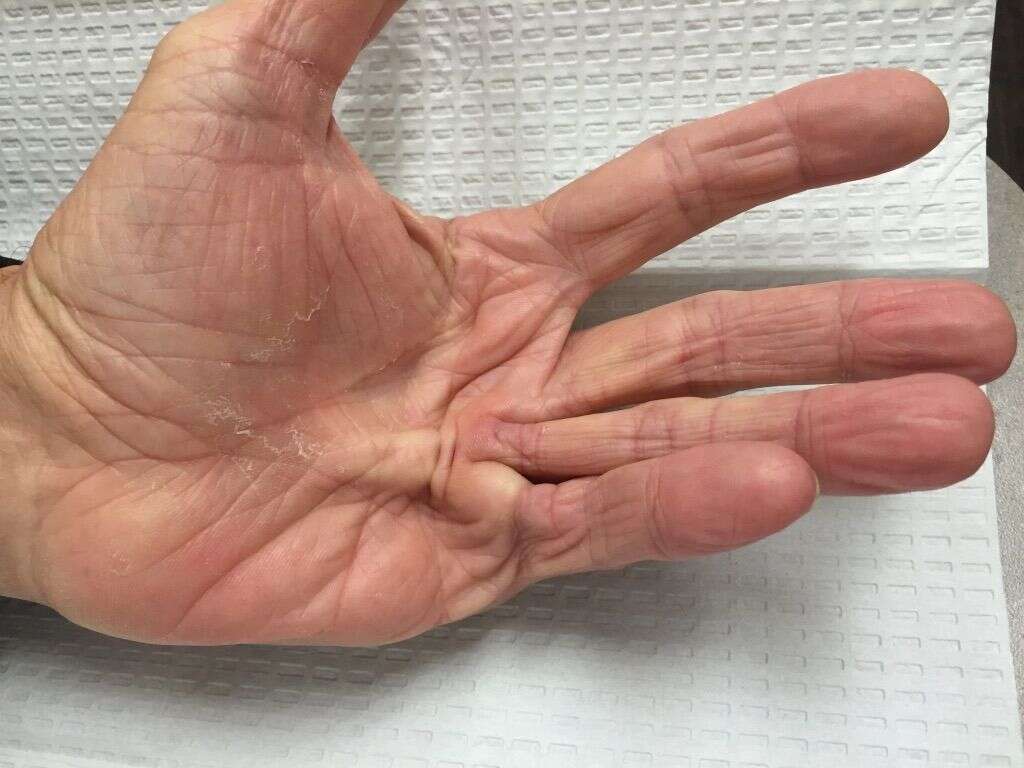

The carpal tunnel is an area in the wrist where a nerve and tendons pass through. Usually, there is ample room for these but, in some instances, the tunnel can be cramped. This can put pressure on the nerves, and this can result in a range of unwelcome symptoms.

One of the symptoms of carpal tunnel syndrome is that the patients fingers turn numb. They will also likely experience other symptoms include pain, a burning sensation, loss of mobility, and muscle weakness. Treatment often involves the use of anti-inflammatory drugs and/or painkillers, while surgery is necessary in some cases.